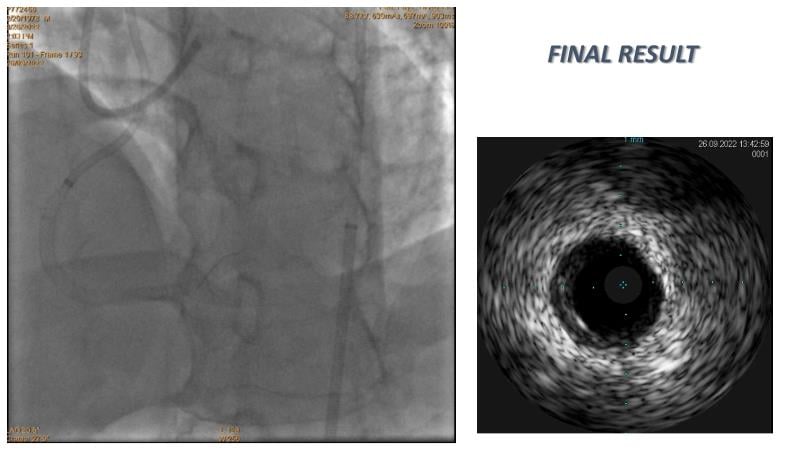

Thanks to the recorded complex CTO case shared in this session, learn how to perform ultra-low contrast PCI, learn what skills are required and tools available to perform ultra-low contrast coronary interventions in CTO, and become aware of the importance of relying on less contrast injections to guide PCI in complex CTO cases.

- To share and discuss a recorded complex CTO case showing how to perform ultra-low contrast PCI